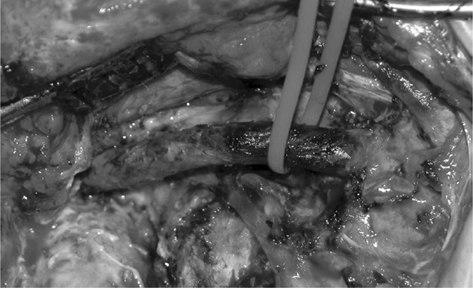

Figure 6 The view of the internal carotid artery. Tumor removal has been completed. Dissection has been carried out down to the stent in an almost bloodless field.

Fig 6